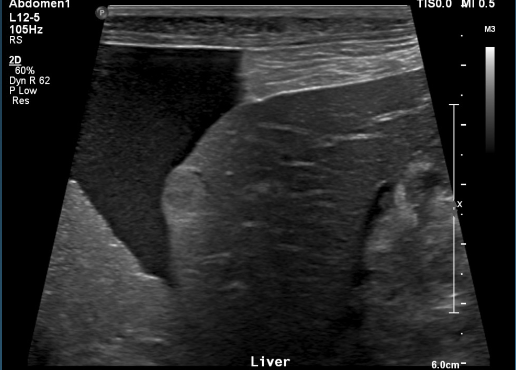

What is shown in these images?

anechoic effusion around liver (left) and bladder (right)